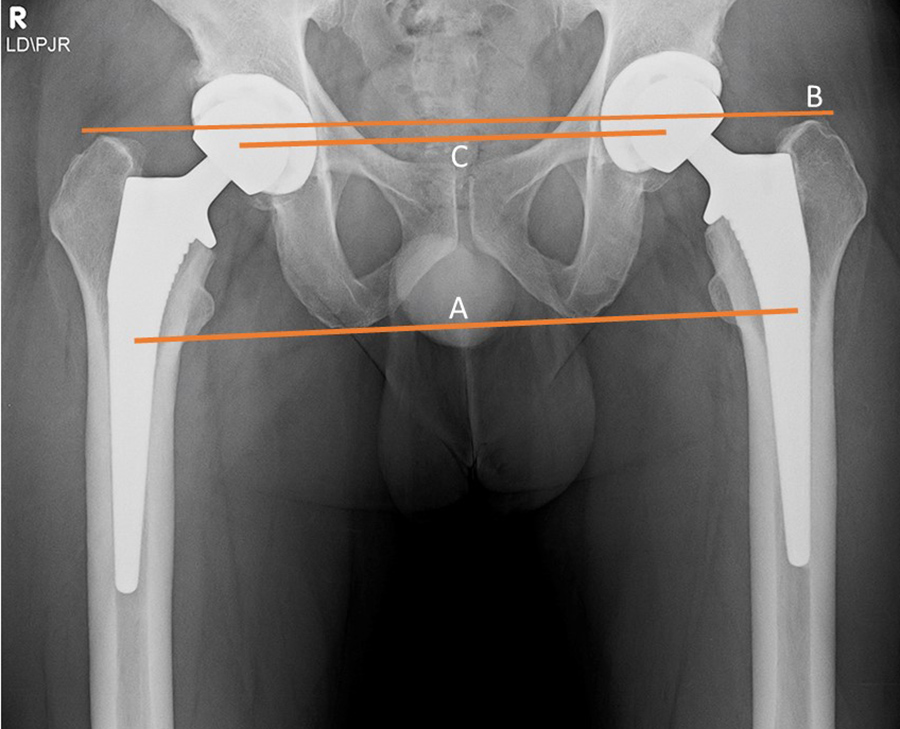

Radiography is essential for the evaluation of hip arthroplasty. A standard AP view of the pelvis and a cross-table lateral view of the pelvis are usually recommended (Jacobson, 2015). A standing AP pevic radiograph is often also included. The preferred position for the acetabular cup is 40°–50° of abduction

from the horizontal plane and 20° anteversion

from the coronal plane (figures: hip arthroplasty evaluation). The prosthetic femoral head is evaluated for its vertical and horizontal positions relative to the contralateral normal hip, when present, in a number of ways (Manaster, 1996; Mulcahy, 2012; Jacobson, 2015; Deshmukh, 2019). One method for evaluating the vertical position of the femoral head is to draw a line (A) tangential to the ischial tuberosities, a line (B) tangential to the tops of the greater tuberosities, and a line (C) through the centers of the femoral heads whether a prosthetic femoral head or a native femoral head. Ideally, these lines should be parallel. To evaluate the horizontal position of the femoral head the distances between the femoral heads and the tops of the acetabular tear drops on each side are measured. Ideally, these distances should be equal.

Limb length discrepancy can also be evaluated by using the anteroposterior standing pevic radiograph to compare contralateral hips. The vertical distance between a horizontal line through the bilateral acetabular teardrops and a parallel line at the level of the centers of the lesser trochanters gives a good indication of relative leg lengths (Deshmukh, 2019).

| Bilateral total hip arthroplasty (THA) |

38 year old man with bilateral THA for advanced osteoarthritis. The distances from a line (C) between the centers of the femoral heads to a line running tangential to the ischial tuberosities (A) should be equal on each side, and the distances between the centers of the femoral heads to a line (B) running tangential to the tops of the greater trochanters should be equal on each side. Lines A, B, C should be parallel. |

38 year old man with bilateral THA for advanced osteoarthritis. The distances from the centers of the femoral heads on each side to the tops of the acetabular tear drops should be equal. |